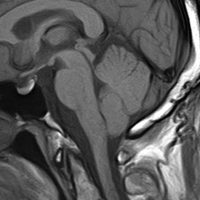

典型的な神経腸嚢胞 neurenteric cyst

左のT2強調画像で等信号,中のT2*で高信号,右はCISS画像です。

T1強調画像では,のう胞周囲の高信号の部分は半固体で,中心部の高信号はドロドロの粘液でした。基本的にガドリニウム増強はされません。まれに薄い膜状に一部が増強されることがあります。

境界明瞭は袋状の腫瘍です。椎骨動脈や脳底動脈を包み込むようにふくらんでいます。